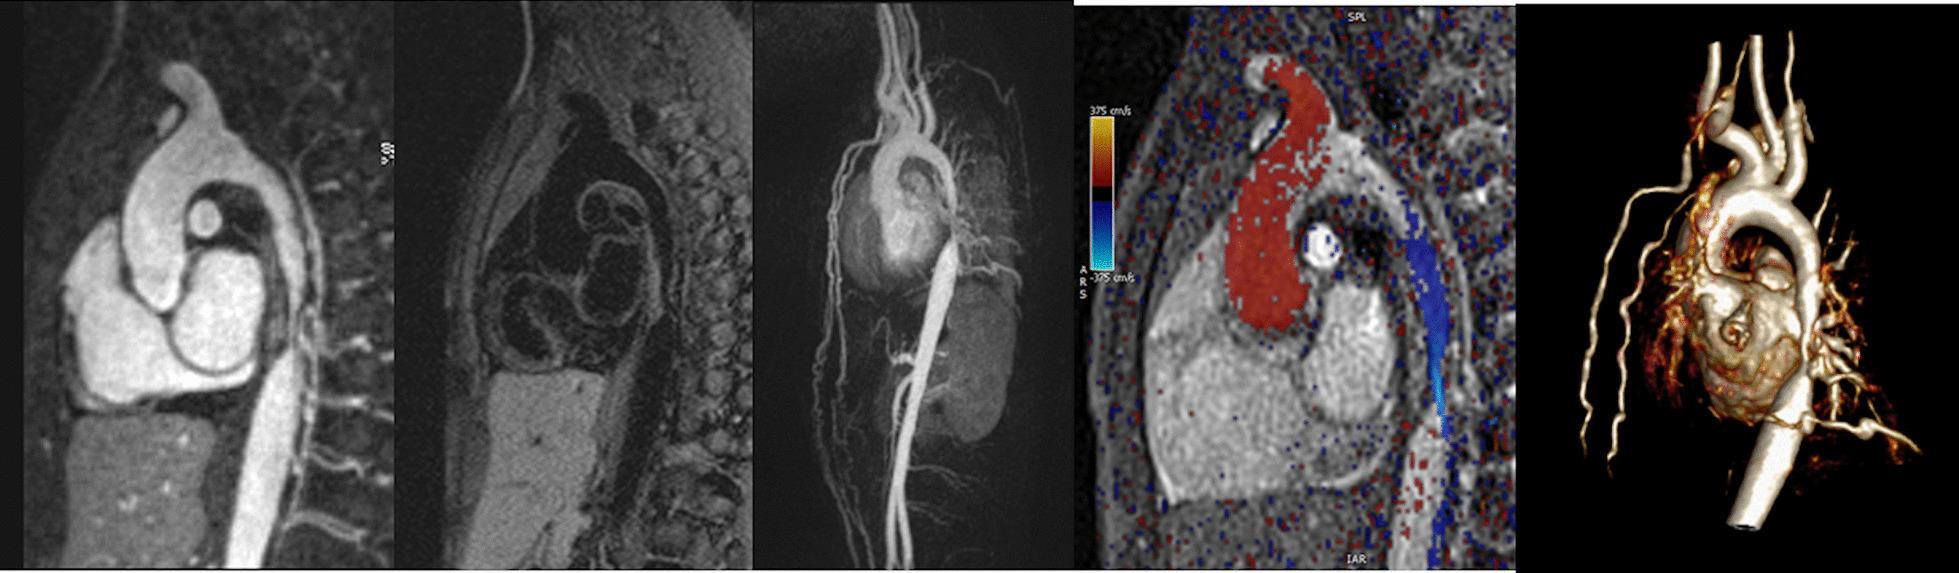

Cardiovascular magnetic resonance (CMR) has been utilized in the management and care of pediatric patients for nearly 40 years. It has evolved to become an invaluable tool in the assessment of the littlest of hearts for diagnosis, pre-interventional management and follow-up care. Although mentioned in a number of consensus and guidelines documents, an up-to-date, large, stand-alone guidance work for the use of CMR in pediatric congenital 36 and acquired 35 heart disease endorsed by numerous Societies involved in the care of these children is lacking. This guidelines document outlines the use of CMR in this patient population for a significant number of heart lesions in this age group and although admittedly, is not an exhaustive treatment, it does deal with an expansive list of many common clinical issues encountered in daily practice.

心血管磁共振(CMR)在儿科患者的管理和护理中已经应用了近 40 年。它已经发展成为评估最小的心脏的宝贵工具,用于诊断、介入前管理和随访。尽管在许多共识和指南文件中提到,但在儿科先天性心脏病和后天性心脏病领域,目前还缺乏一份由众多参与儿童护理的学会共同认可的、最新的、独立的、针对 CMR 使用的大型指南。本指南文件概述了 CMR 在该年龄段的许多心脏病变中的应用,尽管不能说是详尽的治疗方法,但它确实涉及了在日常实践中经常遇到的许多常见临床问题的广泛列表。